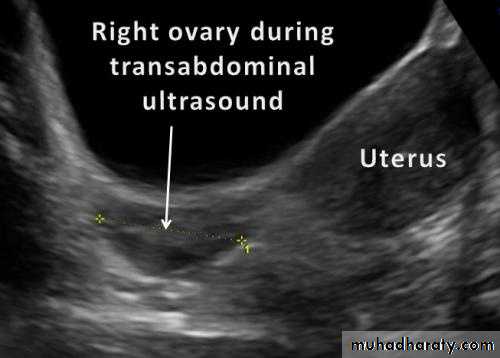

Transabdominal sonography

Is done with a linear or curvilinear array transducer operating at 2.5-3.5 MHz.TAS requires full bladder to displace the bowel out of pelvis.

Other wise gas in the bowel acts as a complete barrier to ultrasound waves.

TAS is best used for large masses like fibroid or ovarian tumorHigher is the frequency of ultrasound wave, better is the image resolution but lesser is the depth of tissue penetration